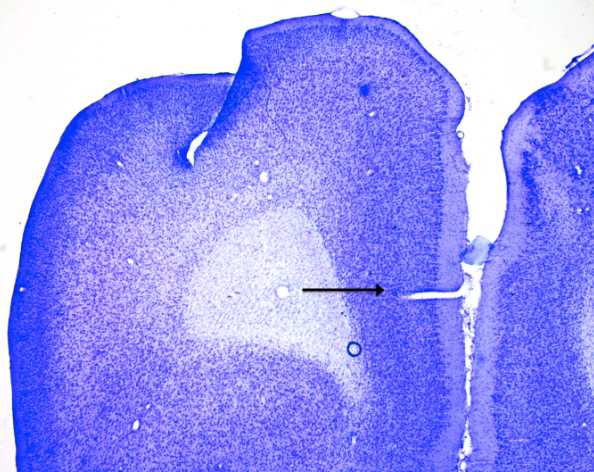

Piriform cortex

knowt flashcard image